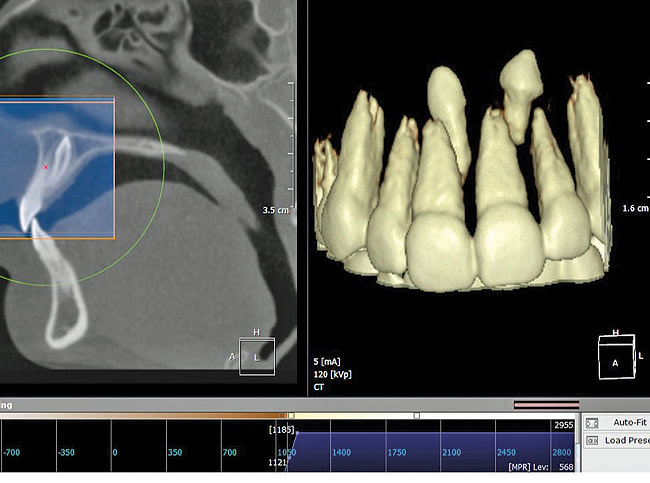

Finally, whether clinicians purchase or simply use the data from CBCT machines in their practice, it is important—perhaps imperative—that they obtain training beyond the manufacturer’s hands-on, in-office introduction. Until trained, a dentist or dental specialist is simply not used to seeing a patient image in the axial plane of section. These types of images, as well as the images in the coronal and sagittal planes and the anatomic data within them, must be mastered before a clinician can feel comfortable using CBCT (Figure 1, Figure 2, and Figure 3).